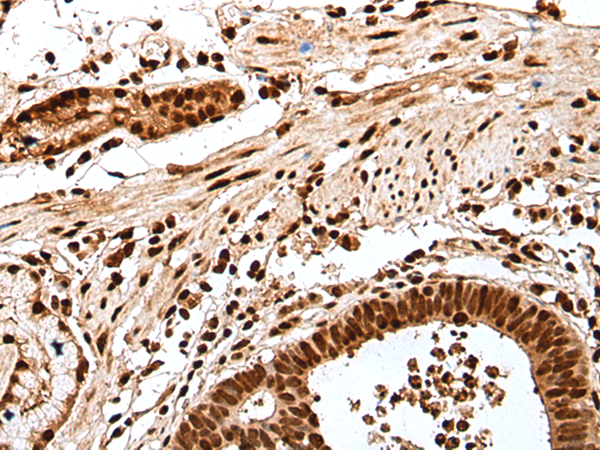

IHC positive control: |

Human esophagus cancer and human gastric cancer |

IHC Recommend dilution: |

25-100 |